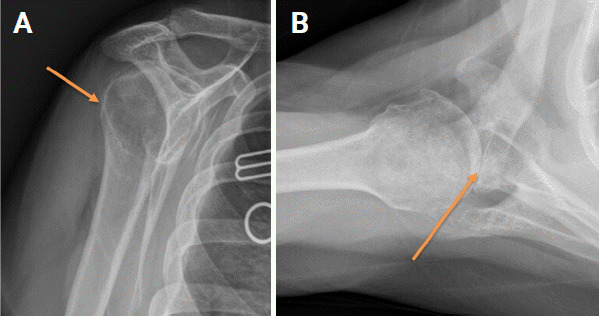

Biconcave (B2) glenoids, characterized by significant posterior glenoid bone loss and a biconcave wear pattern, are a challenging pathology in shoulder surgery. Significant bone defects present in B2 glenoids increases the risk of complications and rates of failure for operative patients with glenohumeral osteoarthritis. Diagnosing this entity is of pivotal importance, and can be accomplished with imaging and a comprehensive clinical investigation. There are no clear-cut guidelines for management, but options include hemiarthroplasty, anatomic total shoulder arthroplasty, and reverse shoulder arthroplasty. In recent years, modern techniques such as corrective reaming, bone grafts, and the use of augmented components have improved patient outcomes. Educating prospective patients is essential for reaching a shared management decision, setting appropriate expectations, and optimizing prognostic outcomes.